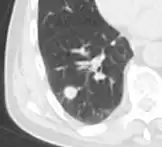

- Location: Upper lobe location is a risk factor for cancer, while a location close to a fissure or the pleura indicates a benign lymph node,[8] especially if having a triangular shape.[9]

- Margin morphology: a spiculated margin is a risk factor for cancer.[8] Benign causes tend to have a well defined border, whereas lobulated lesions or those with an irregular margin extending into the neighbouring tissue tend to be malignant.[10] In particular, spiculations are highly predictive of malignancy with a positive predictive value up to 90%.[9] Also, a "notch sign", which is an abrupt indentation of the nodule, increases the risk of cancer, but may also be found in granulomatous diseases.[9]

-

subpleural nodule.[9] -

Round well-delineated solid lung nodule with smooth border.[9] -

Lobulated nodule.[9] -

Spiculated lung nodule.[9] -

A "notch sign".[9] -

A triangular perifissural node can be diagnosed as a benign lymph node.[9]